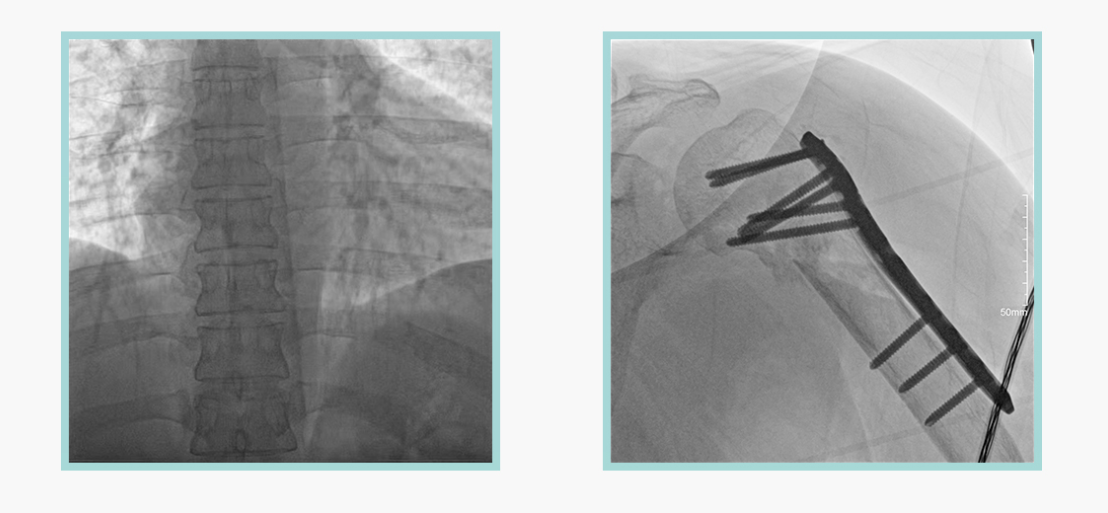

ty8天游平台登录科技悦画移动C臂X线摄影系统,采用了业内技术最尖端的CMOS探测器。基于性能优异的针状CSI闪烁体涂层和高灵敏度的CMOS感光芯片,悦画可以实现在超低X线剂量条件下实现高清晰影像成像,相较于一般的影增移动C臂和平板C臂,动态范围更高,影像的层次感和对比度更好。

在产品的性能参数设计上,悦画的像素可达到200万,空间分辨率可达到3.2线对,采用16bit的影像灰度,悦画在影像后处理上,通过SPI金字塔图像算法,支持摄影、脉冲透视影像、连续透视等多种模式下的影像采集,动态透视影像视频支持保存与回放。双大屏的设计,透视影像支持三档放大,保证临床影像读取的便利。

悦画在影像的伪影处理上,也积累多项图像处理专利技术。通过对植入物的精准识别,悦画能够精准祛除植入物伪影与运动伪影,保证高质量的影像输出,无论是影像的对比度、分辨率(清晰度)相较于市面上的移动C臂产品都更胜一筹。